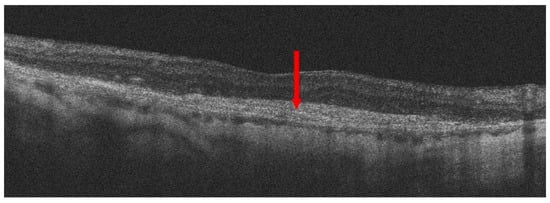

- Spaide, R.F.; Jaffe, G.J.; Sarraf, D.; Freund, K.B.; Sadda, S.R.; Staurenghi, G.; Waheed, N.K.; Chakravarthy, U.; Rosenfeld, P.J.; Holz, F.G.; et al. Consensus Nomenclature for Reporting Neovascular Age-Related Macular Degeneration Data: Consensus on Neovascular Age-Related Macular Degeneration Nomenclature Study Group. Ophthalmology 2020, 127, 616–636. [Google Scholar] [CrossRef]

- Hwang, C.K.; Agron, E.; Domalpally, A.; Cukras, C.A.; Wong, W.T.; Chew, E.Y.; Keenan, T.D.L.; Group, A.R. Progression of Geographic Atrophy with Subsequent Exudative Neovascular Disease in Age-Related Macular Degeneration: AREDS2 Report 24. Ophthalmol. Retin. 2021, 5, 108–117. [Google Scholar] [CrossRef]